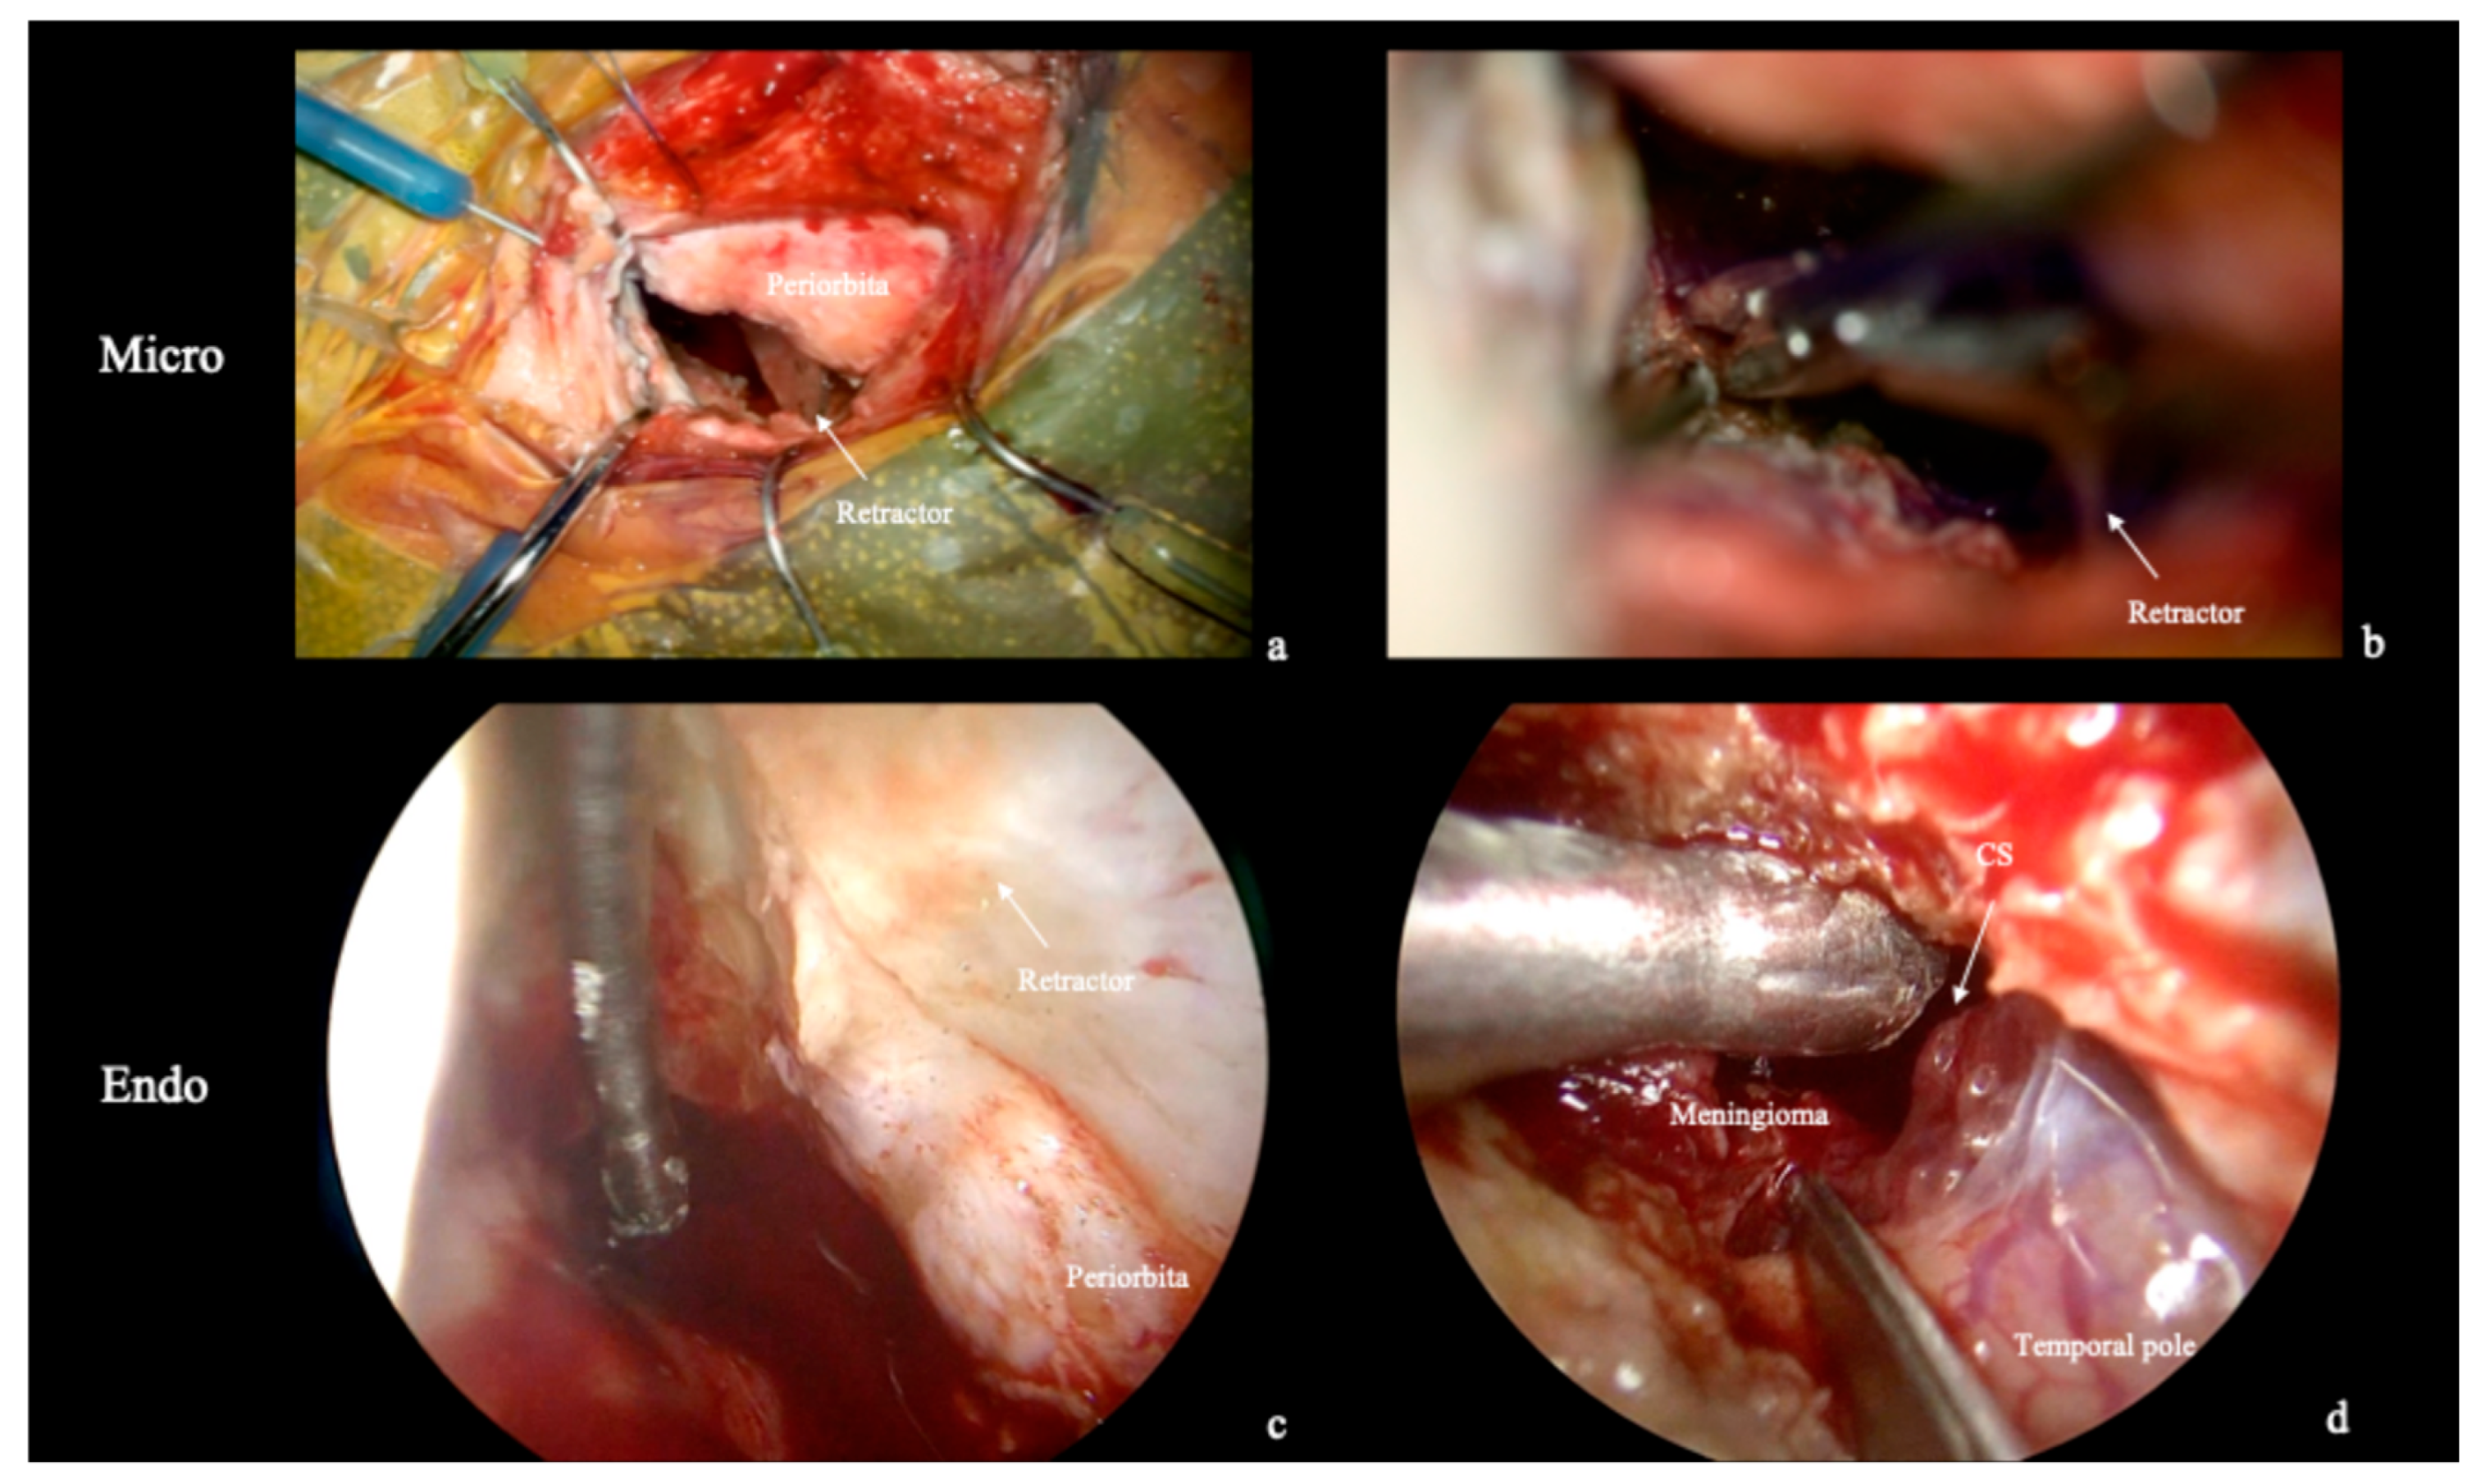

3. Results